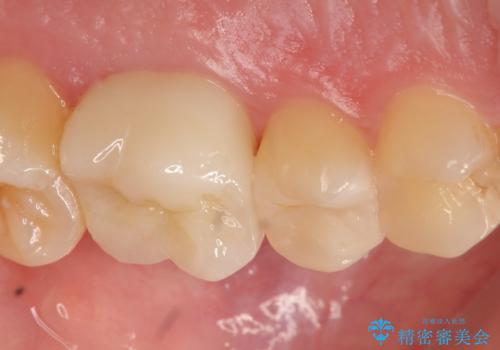

左上6は虫歯を除去後、神経症状がないことを確認し、オールセラミッククラウンによる補綴を行いました。

左上5は古い樹脂と虫歯を除去後、セラミックインレーによる修復を行いました。

当院のセラミックインレーはemaxという強度と審美性に優れた材料を使用しています。

またプレス方式でインレーを製作しているため、削り出しで製作するCADCAMより優れた適合性も持ち合わせており、虫歯が再発しにくい修復物です。

今回用いたオールセラミッククラウンはジルコニアフレームという白い素材の上にセラミックを盛っているため、審美性が非常に高いのが特徴です。

また、ジルコニアは人工ダイヤモンドの材料にも使われているほど高い強度を持っており、そのためオールセラミッククラウンは審美性だけでなく、奥歯やブリッジの補綴も可能とするクラウンです。